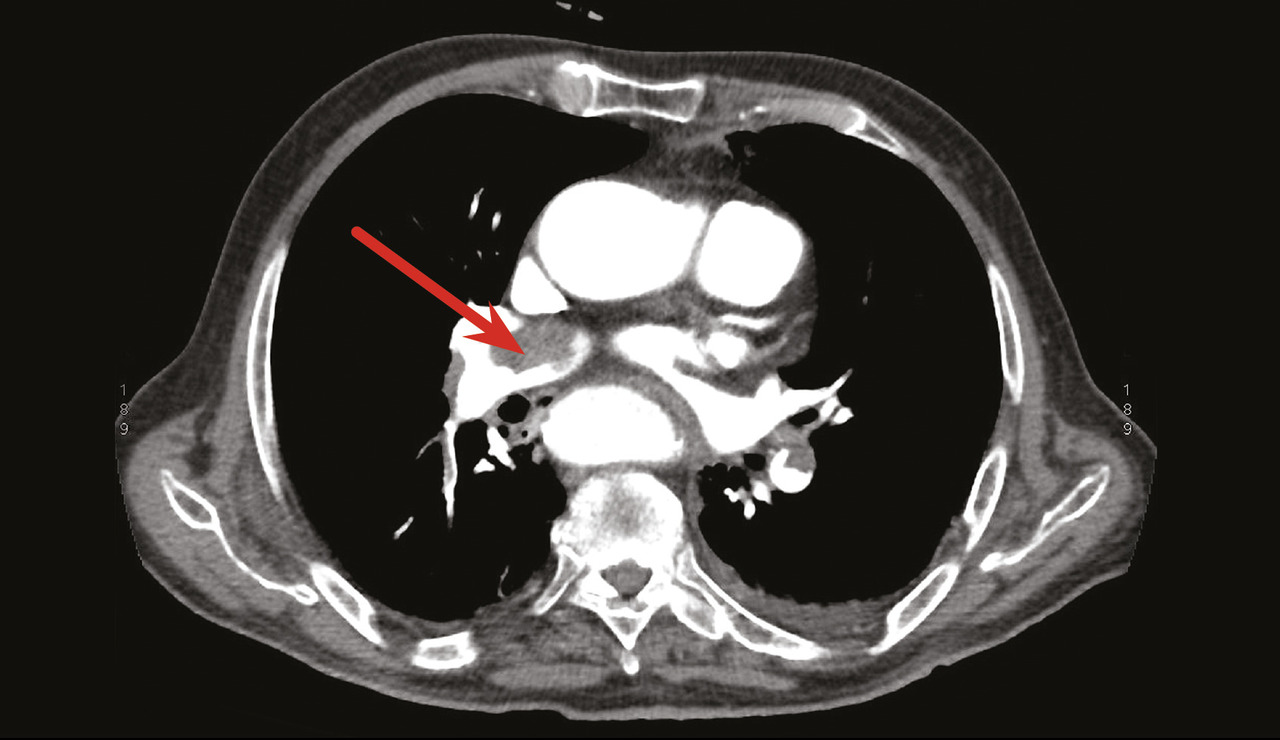

Un angioscanner thoracique objective une embolie pulmonaire bilatérale (fig. 1 ) et une échocardiographie transthoracique montre une masse d’échogénicité hétérogène polylobée mobile mesurant 30 mm, au niveau de l’oreillette droite attachée au septum interatrial (fig. 2 ). L’examen histologique confirme qu’il s’agit d’un thrombus (fig. 3 ). Face à ces résultats, l’indication chirurgicale est posée. Le patient est mis sous traitement anticoagulant, corticothérapie générale et immunosuppresseur.

Un angioscanner thoracique objective une embolie pulmonaire bilatérale (